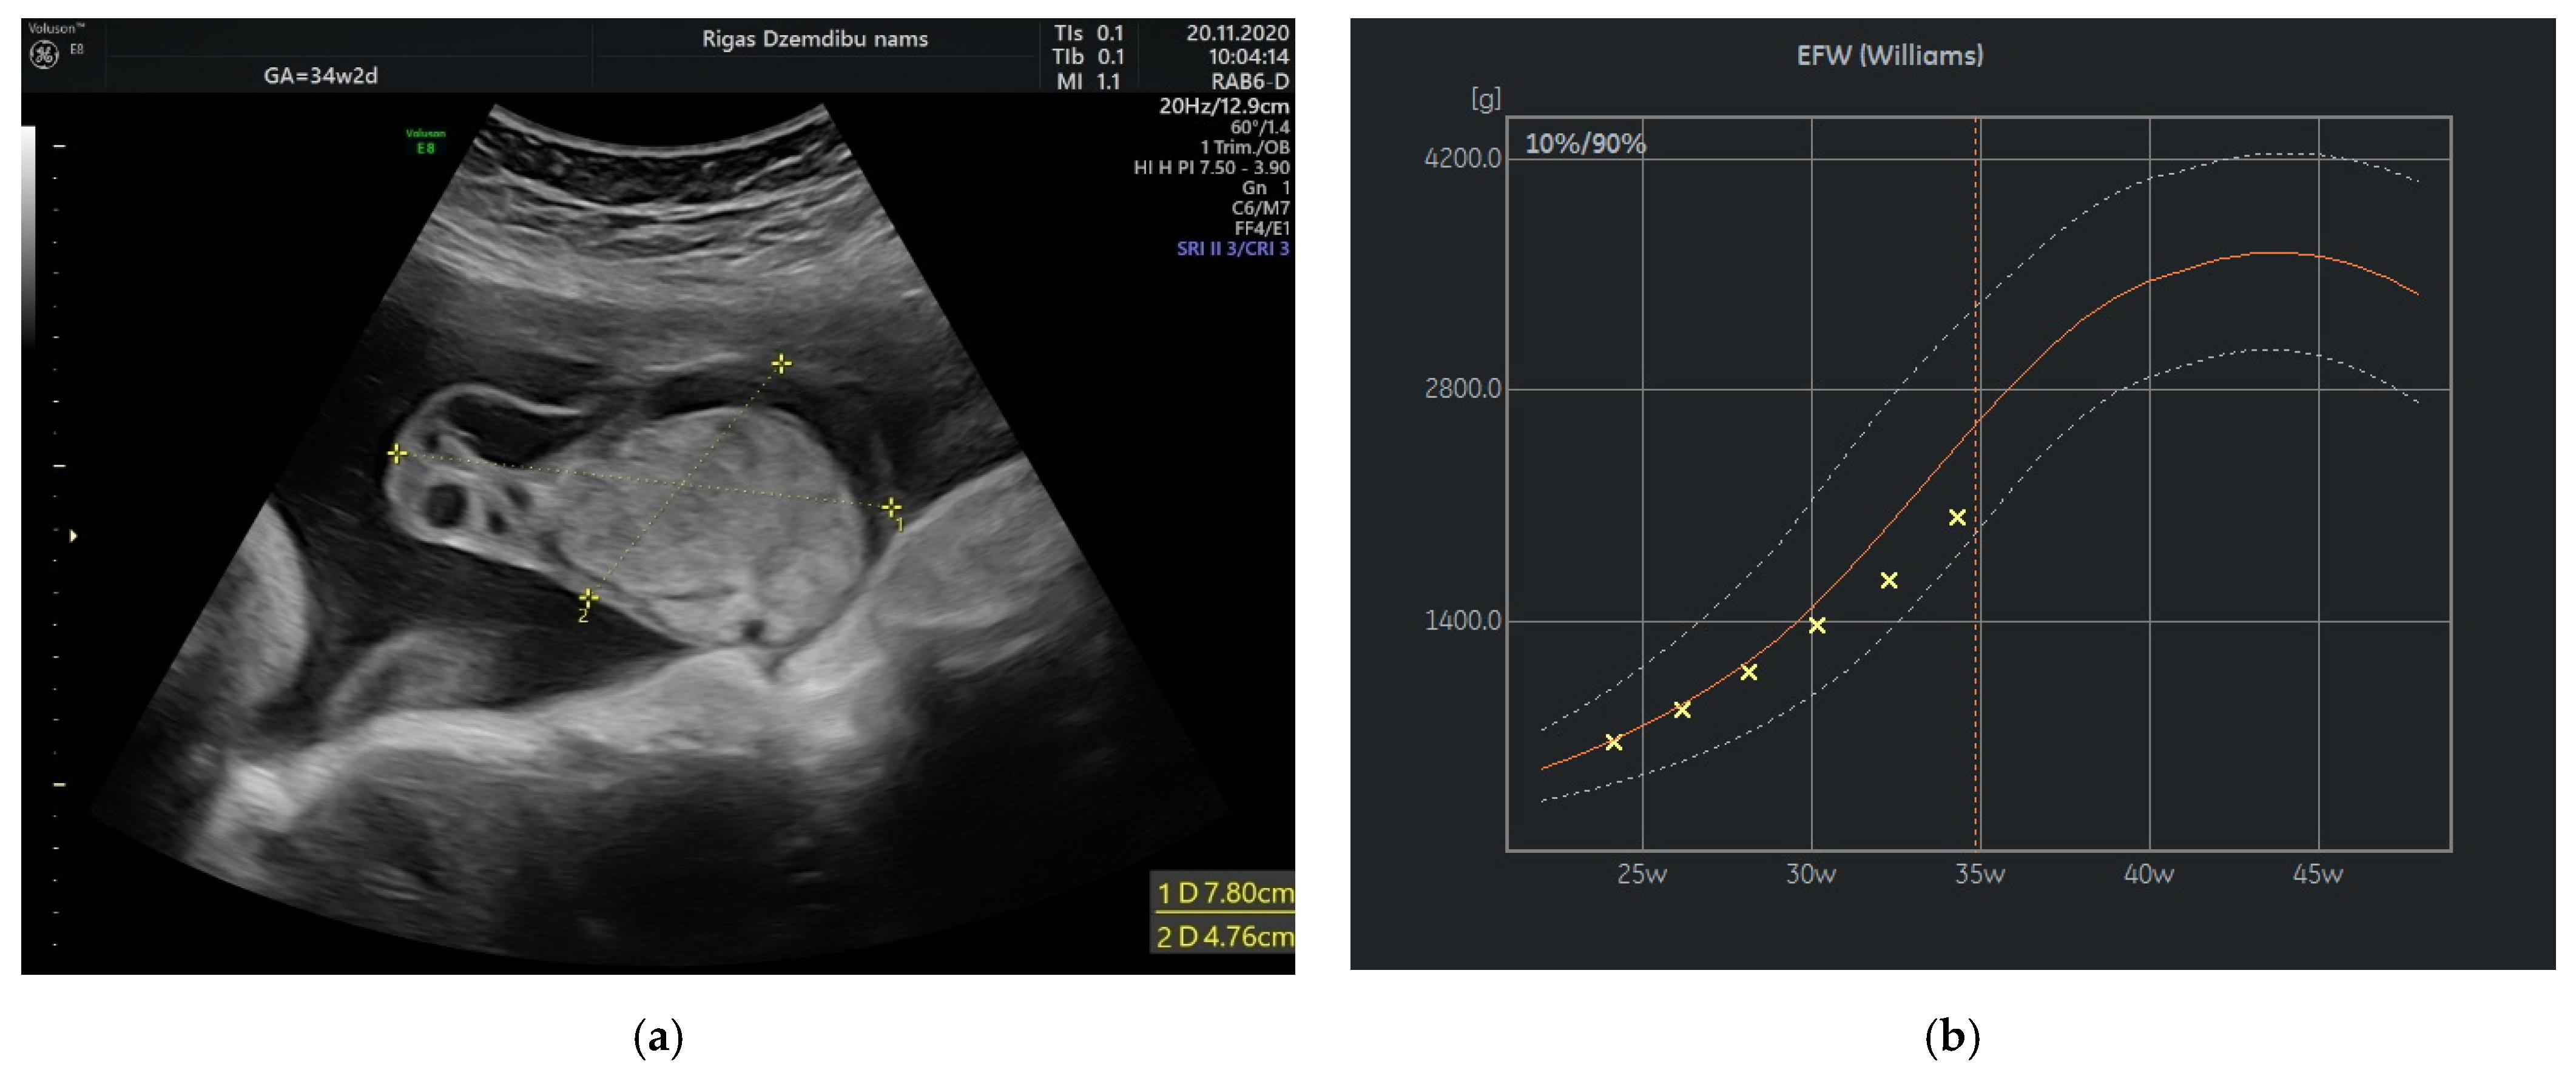

A 28-years-old woman, gravida 2, para 1, was referred to Riga maternity hospital Fetal medicine unit for the second opinion at 24 weeks of gestation. Woman had previously vaginal delivery, complicated by manual placental ablation. She had an otherwise uneventful medical history and denied smoking, use of alcohol, illicit drugs or medications. Detailed ultrasound examination showed a single anatomically normal fetus, with appropriate for gestational age biometric measurements. During the examination the multilocular solid tumor measuring 9.6 × 7.8 × 6.7 cm (265.993 cm3) at the middle portion of the umbilical cord was observed (Figure 1). The differential diagnosis comprised umbilical cord teratoma and angiomyxoma.

Figure 1.

Tumor appearance at 24 + 1 weeks.

The size of the solid component was 3.4 × 2.3 cm and did not change during the pregnancy. The umbilical arteries and vein were running around and through, extra vessels were not observed in the tumor (Figure 2a). At the follow-up, the mass had rapidly enlarged in the size, from 285.32 cm3 at 26 weeks to 1929.36 cm3 at 32 weeks (Figure 2b). As well the reduction of fetal growth was observed from 30th week of gestation (Figure 3b).

Figure 3.

(a) Tumor appearance at 34 + 2 weeks; (b) Growth chart, estimated fetal weight by weeks.

At 34 weeks of gestation reduction in the size of tumor’s cystic component with freely floating superficial membranes was observed (Figure 3a). That resembles the process of rupture of the membranes without any signs of bleeding. Normal ACM PSV (49.4 cm/s) was recorded during examination of the fetus. At that time the umbilical mass decreased in size enormously and measured 120.45 cm3.